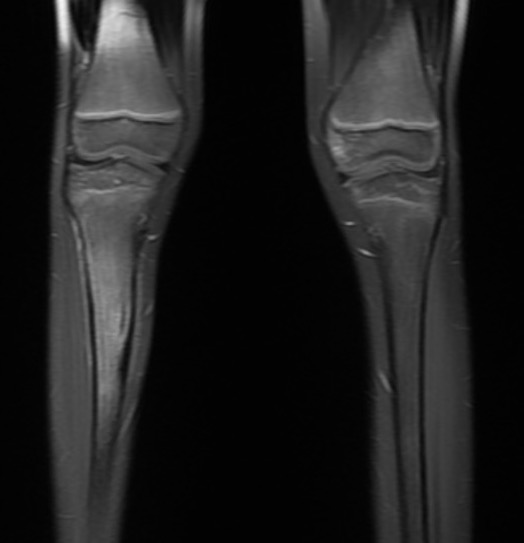

Osteoid osteoma tibia